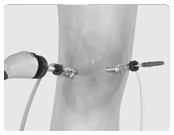

Robotic-assisted knee replacement surgery is an alternative to the conventional knee replacement procedure. It is performed using robotic-arm technology that allows your surgeon to precisely perform the surgery through a smaller incision as compared to traditional surgery. Dr. Liddell performs both total knee and partial knee replacement in a minimally invasive manner with precision under robotic assistance.